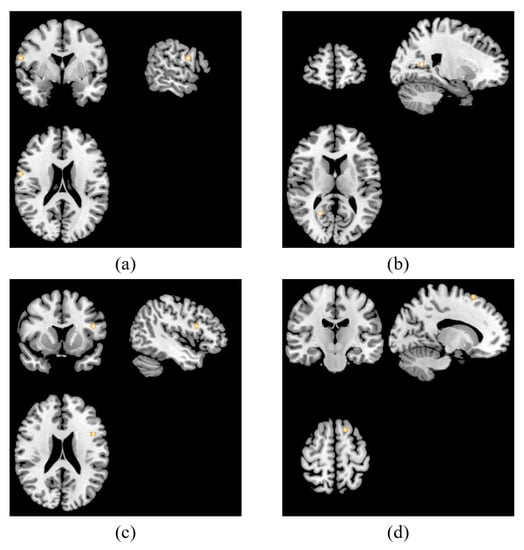

| Region | Cluster Size (mm3) | MNI Coordinates | ALE | p Value | Z Score | BA | ||

|---|---|---|---|---|---|---|---|---|

| x | y | z | max. | |||||

| Main analysis | ||||||||

| Right precentral gyrus | 352 | 60 | 0 | 20 | 0.0078 | 0.0000201 | 4.106458 | 6 |

| Right posterior cingulate | 288 | 21 | 57 | 12 | 0.0075 | 0.0000379 | 3.957385 | 30 |

| Left inferior frontal gyrus | 288 | −46 | 12 | 22 | 0.0073 | 0.0000710 | 3.804717 | 9 |

| Left middle frontal gyrus | 288 | −16 | −18 | 62 | 0.0073 | 0.0000710 | 3.804717 | 6 |

| Resting-state studies | ||||||||

| Right precentral gyrus | 480 | 60 | 0 | 21 | 0.0078 | 0.0000137 | 4.194821 | 6 |

| Right posterior cingulate | 448 | 21 | 57 | 12 | 0.0075 | 0.0000299 | 4.013568 | 30 |

| Left inferior frontal gyrus | 448 | −46 | 12 | 22 | 0.0073 | 0.0000611 | 3.842041 | 9 |

| Left superior frontal gyrus | 448 | −15 | −18 | 63 | 0.0073 | 0.0000610 | 3.842041 | 6 |

| Task-related studies | ||||||||

| Right middle frontal gyrus | 384 | 48 | 20 | 18 | 0.0063 | 0.0000038 | 4.476675 | 46 |

| Left sub-gyrus | 360 | −18 | 4 | 52 | 0.0062 | 0.0000156 | 4.165172 | 6 |

| Left middle frontal gyrus | 352 | −32 | 2 | 42 | 0.0060 | 0.0000238 | 4.066664 | 6 |

| Left posterior cingulate | 344 | −16 | −60 | 24 | 0.0062 | 0.0000156 | 4.165172 | 31 |